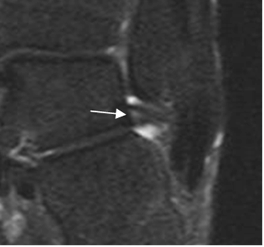

Fig 62. Esguince grado II.

A y B: RM axial en T2. LPAA irregular y con interrupción de algunas fibras, por ruptura parcial.